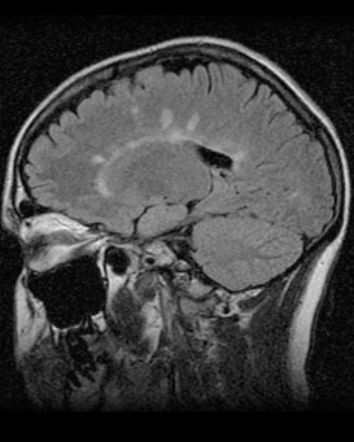

Se pueden apreciar _______ en T2 y FLAIR.

¿Qué hallazgos en RM se pueden encontrar en la esclerosis múltiple,?